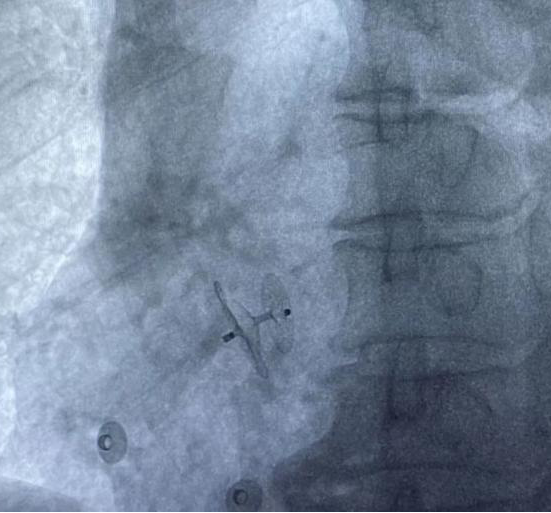

經(jīng)過(guò)充分的術(shù)前準(zhǔn)備和溝通,以及制定術(shù)中緊急預(yù)案后,心內(nèi)科介入手術(shù)團(tuán)隊(duì)為成某實(shí)施卵圓孔未閉(PFO)介入封堵手術(shù),手術(shù)時(shí)長(zhǎng)不足半小時(shí),術(shù)后患者頭痛明顯緩解。

經(jīng)股靜脈送入封堵傘 封堵傘成功釋放